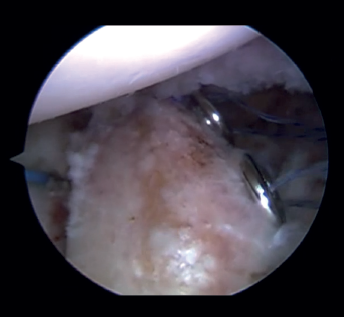

Introduction of the glenoid guide and positioning of the sheaths

(Figures 2 and 3)

Arthroscope is introduced through the anterosuperior portal, and the glenoid guide is introduced through the posterior portal, and passed paralel to the glenoid surface until the hook is located at the centre of the bone defect. The guide is secured with two cannulas inserted through two small accessory incisions, until connecting with the posterior cortical layer. Both cortical layers are drilled through them using a 2.8 mm drill fitted with a sheath so that on withdrawing the drill the sheath is positioned at drilling level. This step is made twice to introduce two sheaths: one above and the other below the glenoid guide hook and spaced 10 mm apart. Through these sheaths we advance two monofilament loops that are retrieved sequentially through the anterior portal for subsequent passing of the graft. At this point we can remove both sheaths and the glenoid guide, taking care to prevent the guide hook from coming into contact with the glenoid surface in order to avoid damaging to the cartilage.

Figure 3. View from the anterosuperior portal (left shoulder). Monofilaments inserted through the sheaths from posterior to anterior for subsequent passing of the threads that will introduce the graft.